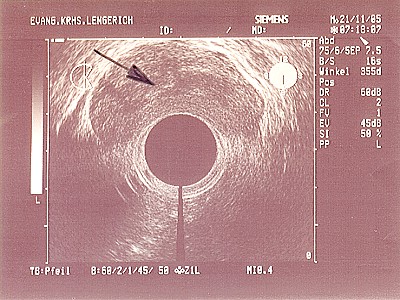

Abb. 6: Bösartiger Tumor des unteren Mastdarmes T3 - T4 mit einem vergrößerten Lymphknoten, der alle Darmschichten überschritten hat. Abb. 6: Bösartiger Tumor des unteren Mastdarmes T3 - T4 mit einem vergrößerten Lymphknoten, der alle Darmschichten überschritten hat.